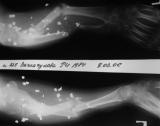

Огнестрельный дефект предплечья

На рентгенограммах приведены картинки - одна без вмешательств, другая в условиях ручной тракции по оси предплечья. Кисть была полностью нефункциональна - сгибательные контрактуры всех пальцев, выраженный отек кисти, Было решено, что тактику лечения определим после попытки восстановления функции кисти. На сегодня - полное восстановоение объема движений в пальцах за исключением активного отведения 1 пальца. Больная даже вяжет на спицах. Больная не очень дисциплинирована, выписывалась из стационара за алкогольные радости, длительное лечение с использованием ЧКДОС мало реально.